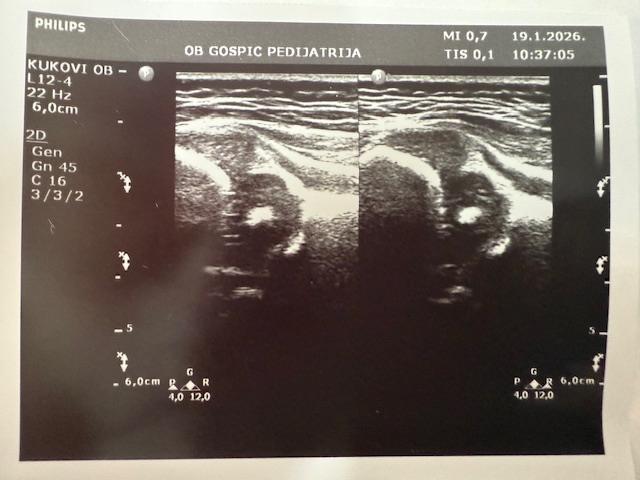

Posebnu vrijednost Dječjeg odjela predstavlja Ultrazvučna ambulanta u kojoj se već punih 20 godina provodi jedinstveni dojenački probir na bolesti i razvojne poremećaje mozga te razvojne poremećaje zgloba kuka. Riječ je o jedinom takvom sustavnom probiru u Hrvatskoj, koji se provodi po principu skrininga, odnosno usmjeren je na otkrivanje poremećaja kod naizgled zdrave djece. Svako dojenče rođeno u Općoj bolnici Gospić obavlja oba pregleda kao standardni dio zdravstvene skrbi.

Probir provodi pedijatrica i ravnateljica bolnice dr. Sandra Čubelić, a analiza pokazuje da se godišnje obavi oko 1200 ultrazvučnih pregleda. U proteklih 20 godina provedeno je približno 25 tisuća pregleda, što ovaj program svrstava među najznačajnije dugoročne zdravstvene nadstandarde u regiji. Iako su se pregledi u početku obavljali u novorođenačkoj dobi, danas je uobičajeno da se provode kada dojenče navrši mjesec dana.

Svrha probira je rano otkrivanje poremećaja, prije nego se pojave simptomi ili znakovi bolesti. Upravo zahvaljujući tom pristupu, kod dvoje djece pravodobno je izvedena operacija mozga prije nego što su se razvile bilo kakve smetnje psihomotornog razvoja. Blaži razvojni poremećaji otkrivaju se znatno češće, što omogućuje pravodobno praćenje i liječenje. Kod zgloba kuka razvojni poremećaji se razlikuju po težini – luksacije i subluksacije javljaju se rjeđe, dok su displazije češće. Cilj pregleda je započeti liječenje prije nego dijete prohoda, jer se poremećaji otkriveni kasnije liječe teže, dugotrajnije i nerijetko operativnim zahvatima.